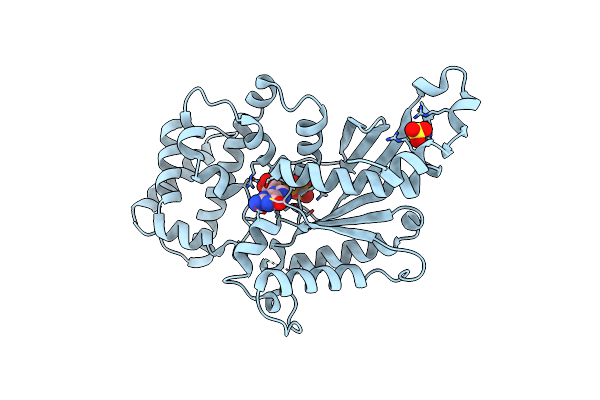

Beta-Hydroxyacyl-Acyl Carrier Protein Dehydratase (Fabz) From Plasmodium Falciparum In Complex With Nas21

Organism: Plasmodium falciparum

Method: X-RAY DIFFRACTION Resolution:3.10 Å Release Date: 2012-02-29 Classification: LYASE/INHIBITOR Ligands: GOL, PEG, CL, S21, PO4 |

Beta-Hydroxyacyl-Acyl Carrier Protein Dehydratase (Fabz) From Plasmodium Falciparum In Complex With Nas91

Organism: Plasmodium falciparum

Method: X-RAY DIFFRACTION Resolution:2.75 Å Release Date: 2012-02-29 Classification: LYASE/INHIBITOR Ligands: GOL, PO4, K91 |

Beta-Hydroxyacyl-Acyl Carrier Protein Dehydratase (Fabz) From Plasmodium Falciparum In Complex With Nas91-10

Organism: Plasmodium falciparum

Method: X-RAY DIFFRACTION Resolution:2.70 Å Release Date: 2012-02-29 Classification: LYASE/INHIBITOR Ligands: GOL, KM0 |

Beta-Hydroxyacyl-Acyl Carrier Protein Dehydratase (Fabz) From Plasmodium Falciparum In Complex With Nas91-11

Organism: Plasmodium falciparum

Method: X-RAY DIFFRACTION Resolution:2.60 Å Release Date: 2012-02-29 Classification: LYASE/INHIBITOR Ligands: GOL, KM1 |